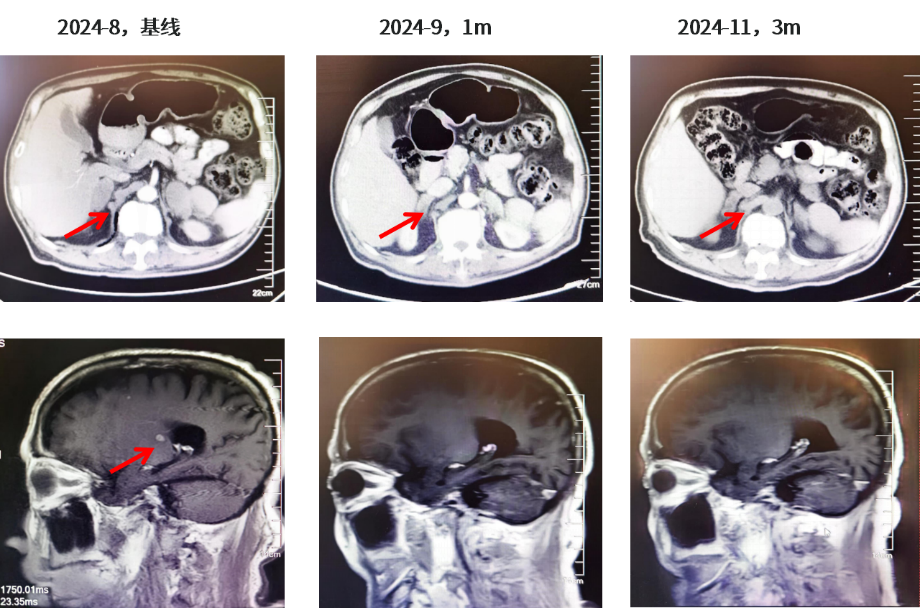

患者于2024年8月14日-2024年11月接受伏美替尼80mg QD联合伯瑞替尼100mg BID靶向治疗,治疗1个月后2024年9月11日复查右肺肺门靶病灶明显缩小(57mm→25mm),肾上腺病灶明显缩小(右侧48mm→36mm;左侧46mm→34mm),疗效评估达PR。头颅MR示颅内病灶消失,疗效评价达CR。患者有肺间质纤维化既往史,右肺间质性改变加重,不除外药物相关不良反应,患者无明显不适症状。主要不良反应为I级间质性肺炎,I级肌酐增高。肿瘤标志物:CYFRA21-1由40.61降至3.11,CA19-9由1575降至23.65。

图3.胸部CT结果(2024.08基线、2024.09、2024.11)

图4.肾上腺CT结果及颅脑MR结果(2024.08基线、2024.09、2024.11)

行靶向药物剂量调整:2024年12月-2025年2月一线伏美替尼80mg QD联合伯瑞替尼100mg QD(必要时隔天一次)靶向治疗,并对症治疗:氨溴索+乙磺酸尼达尼布+乙酰半胱氨酸;增强检查改为平扫,加强水化、利尿,使用尿毒清颗粒治疗。疗效整体维持PR,颅内维持CR;但肿瘤标志物较前增高(CYFRA21-1由3.11升至4.44,CA19-9由23.65升至107.7)。2025年2月复查双侧肾上腺转移瘤较前略增大变饱满(右侧长径42mm,左侧长径38mm),提示疾病进展(PD)趋势,未达PD标准。